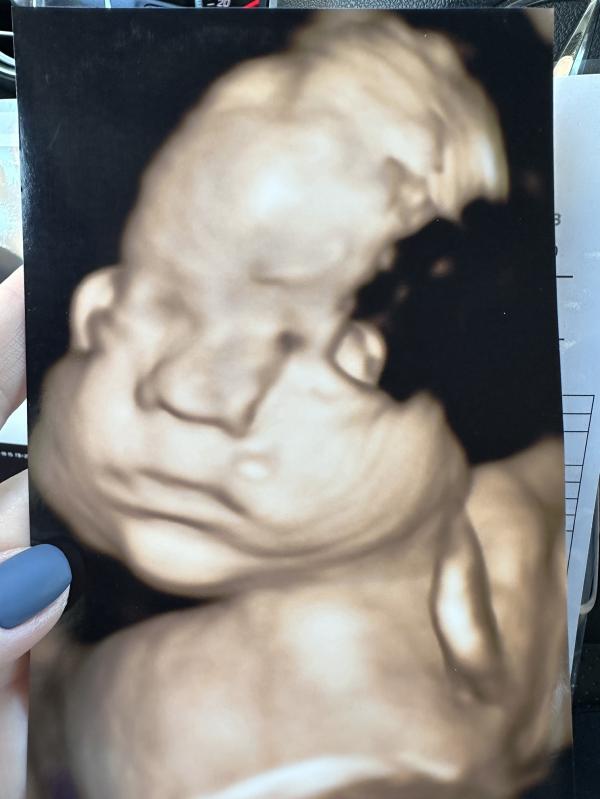

Третий скрининг прошел, сегодня 29н 6дн, малышка развивается по сроку, вес 1571г +/-200г. Есть не тугое обвитие, пуповина лежит прямо на носике, поэтому на фото он не ровненький. Рукой дочка держит пуповину) сказали через пару недель прийти на доплер, посмотреть кровотоки, есть небольшие изменения, но сказали не пугаться, чаще всего при перепроверке уже все в норме бывает. Плацента хорошая. Лежит головой вниз. Дочка уже с прической, первая тоже родилась с косичками)

У Савинчевой Веры Сергеевны, клиника 9 месяцев, мне понравилась, приятная врач